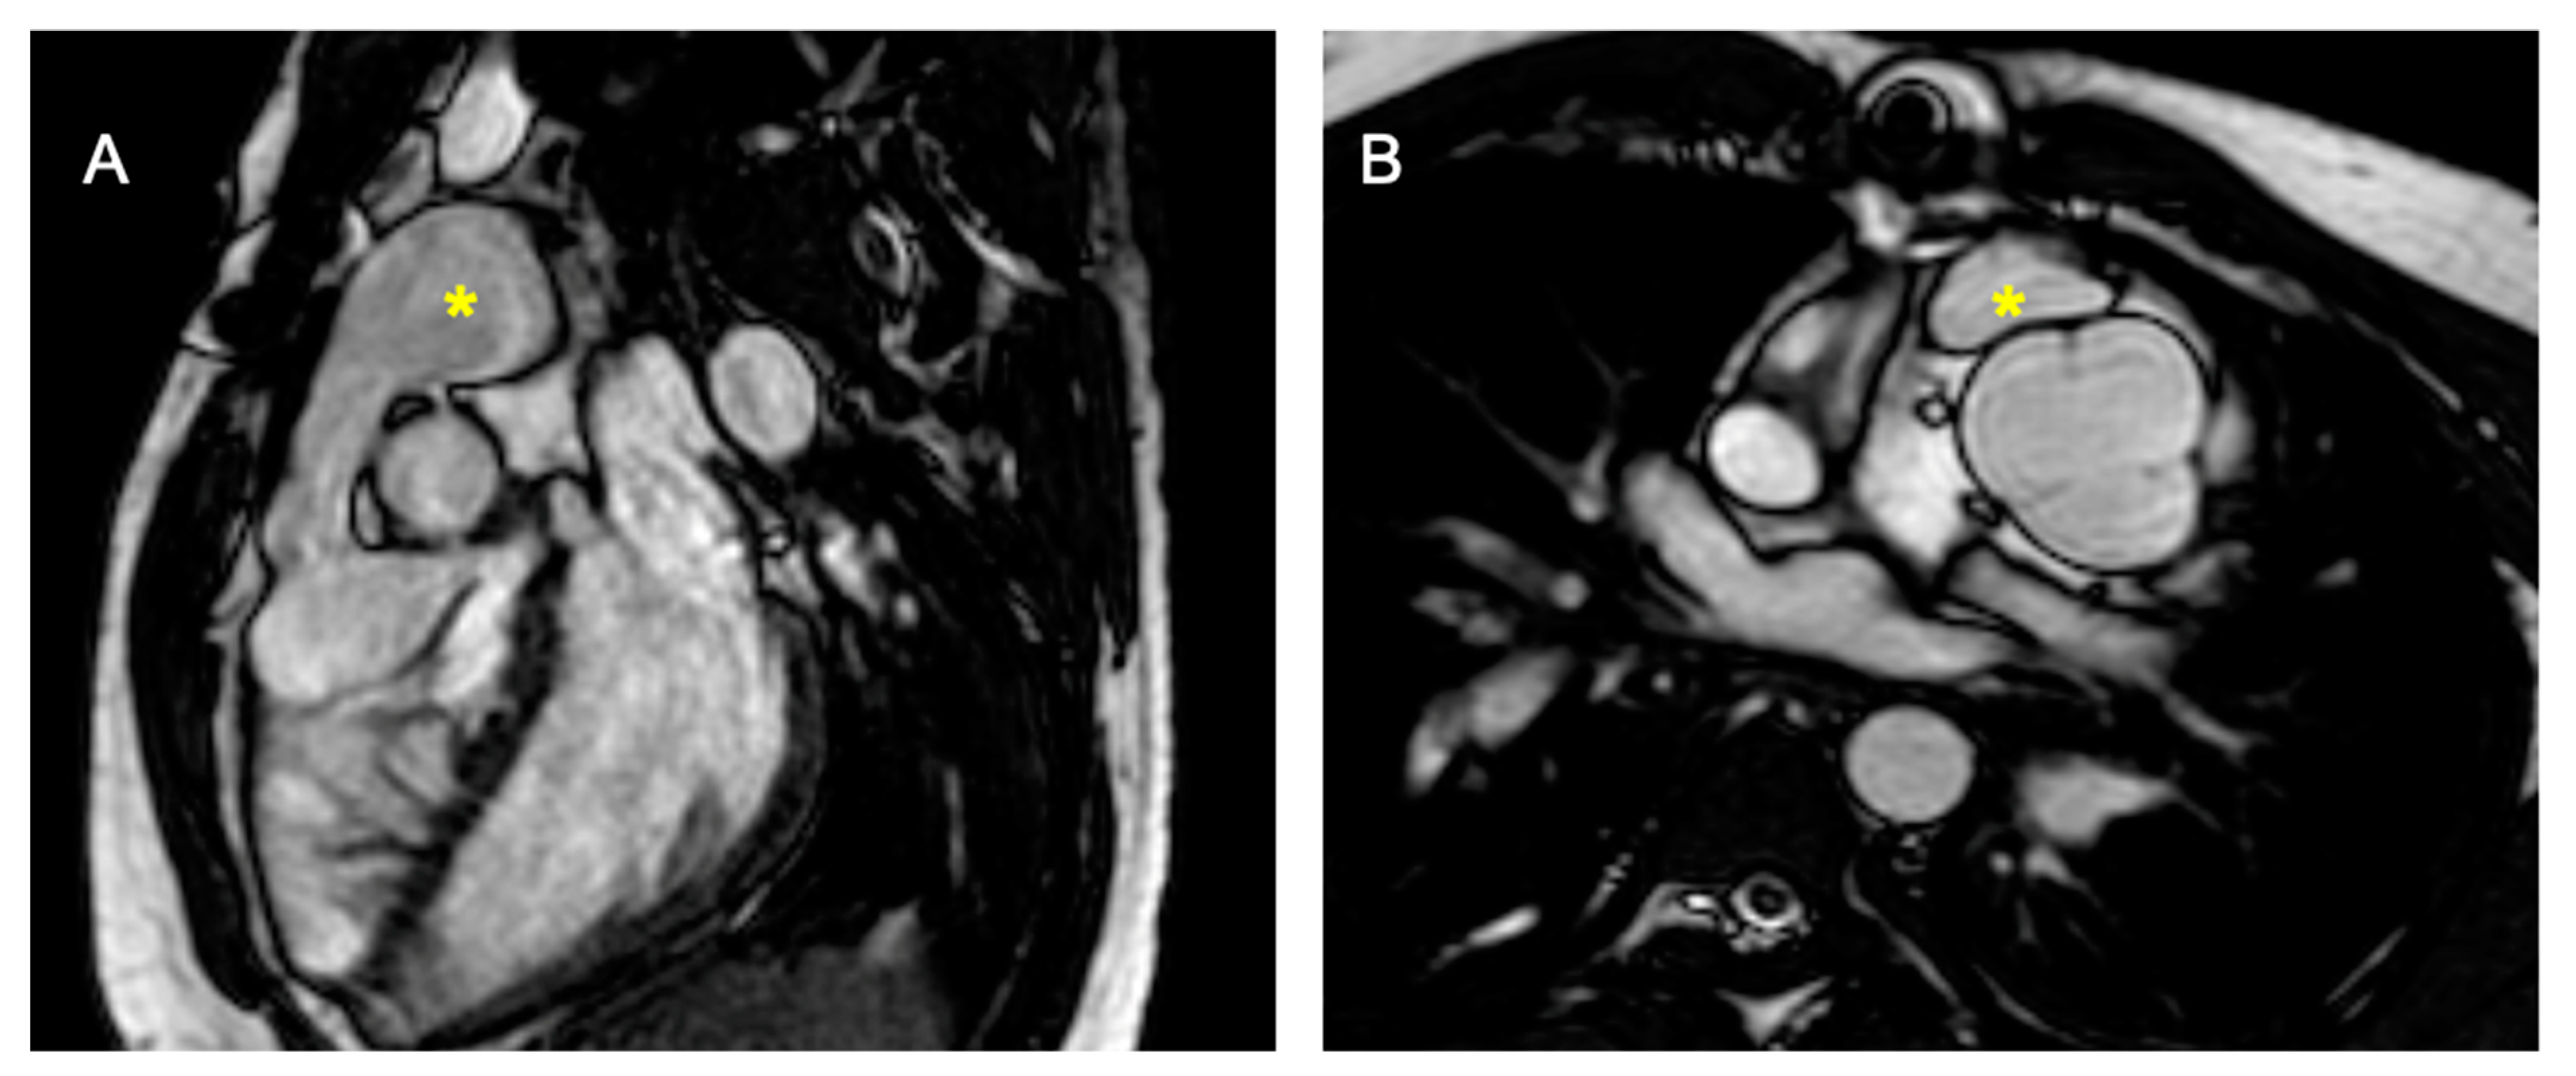

Figure 5.

D-TGA with pulmonary stenosis/atresia post-placement of the right ventricle to pulmonary artery (RV-PA) conduit. (A) shows a sagittal section, and (B) displays a transverse section, both highlighting the pulmonary conduit (marked with *).